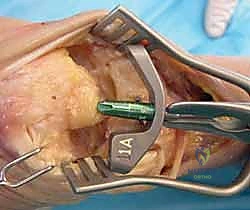

Carpal preparation requires exacting precision. Using the Maestro system as the archetype, the carpal resection guide is positioned to allow resection of 2 to 3 mm of the capitate head. It is provisionally held in position with two 0.062-inch Kirschner wires. The first wire is placed into the capitate neck and the second into the metaphysis of the third metacarpal, ensuring that the guide is perfectly parallel to the third metacarpal axis. With proper placement, the ulnar guide wing will lie close to the triquetrum–hamate articulation, and the radial wing will bisect the scaphoid at its distal third.

With the wrist held in neutral, the radius is scored through the cutting slot in the guide to provide a reference for the distal radial resection. The thumbscrew on the carpal resection guide is loosened to allow insertion of the radial resection guide boom. Following radial resection, the scaphoid, capitate head, hamate edge, and triquetrum are resected at a precise 90-degree angle to the axis of the forearm jig. The trial carpal plate is provisionally determined by the curvature and width of the remaining proximal carpal surface; it must lie flush with the hamate and proximal capitate surfaces. Unlike older designs, it is not always necessary to attempt fusion of the distal pole of the scaphoid to the surrounding carpus. The Maestro Wrist has a provision to replace the entire scaphoid using a carpal plate incorporating a modular radial augment, of which three separate sizes are available.

Following capitate reaming, the chosen carpal plate and stem are assembled and inserted into the capitate and seated onto the resected carpal surface. The carpal plate is anchored to the carpus with a radial screw that optimally does not penetrate the second metacarpal, and a second screw placed ulnarly into the hamate. This construct ensures stable distal fixation while avoiding the deleterious lever arm of a long metacarpal stem. Trial reductions are performed to assess stability, range of motion, and impingement. Once kinematics are confirmed, the definitive ultra-high-molecular-weight polyethylene (UHMWPE) body—which is direct compression molded onto a cobalt chrome alloy radial body—is impacted. The capsule and extensor retinaculum are meticulously repaired to prevent extensor tendon bowstringing and provide a robust soft tissue envelope over the implant.